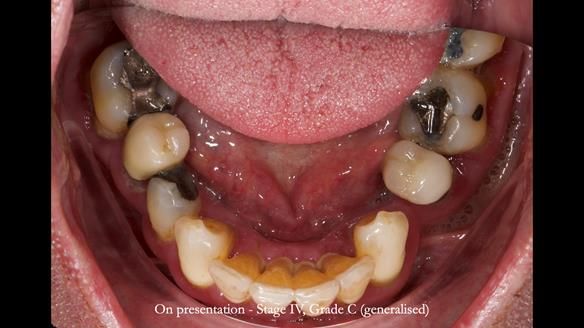

Jeremy’s upper bridge, supported by the canine teeth (13 and 23), was failing both aesthetically and functionally.

- On smiling, the bridge was clearly visible and did not look natural, as the ceramic had been ground back.

- Functionally, the bridge was unstable, due to Periodontitis – Stage IV, Grade C (generalised).

- The upper molars (UR7 and UL7) had also failed and required removal.